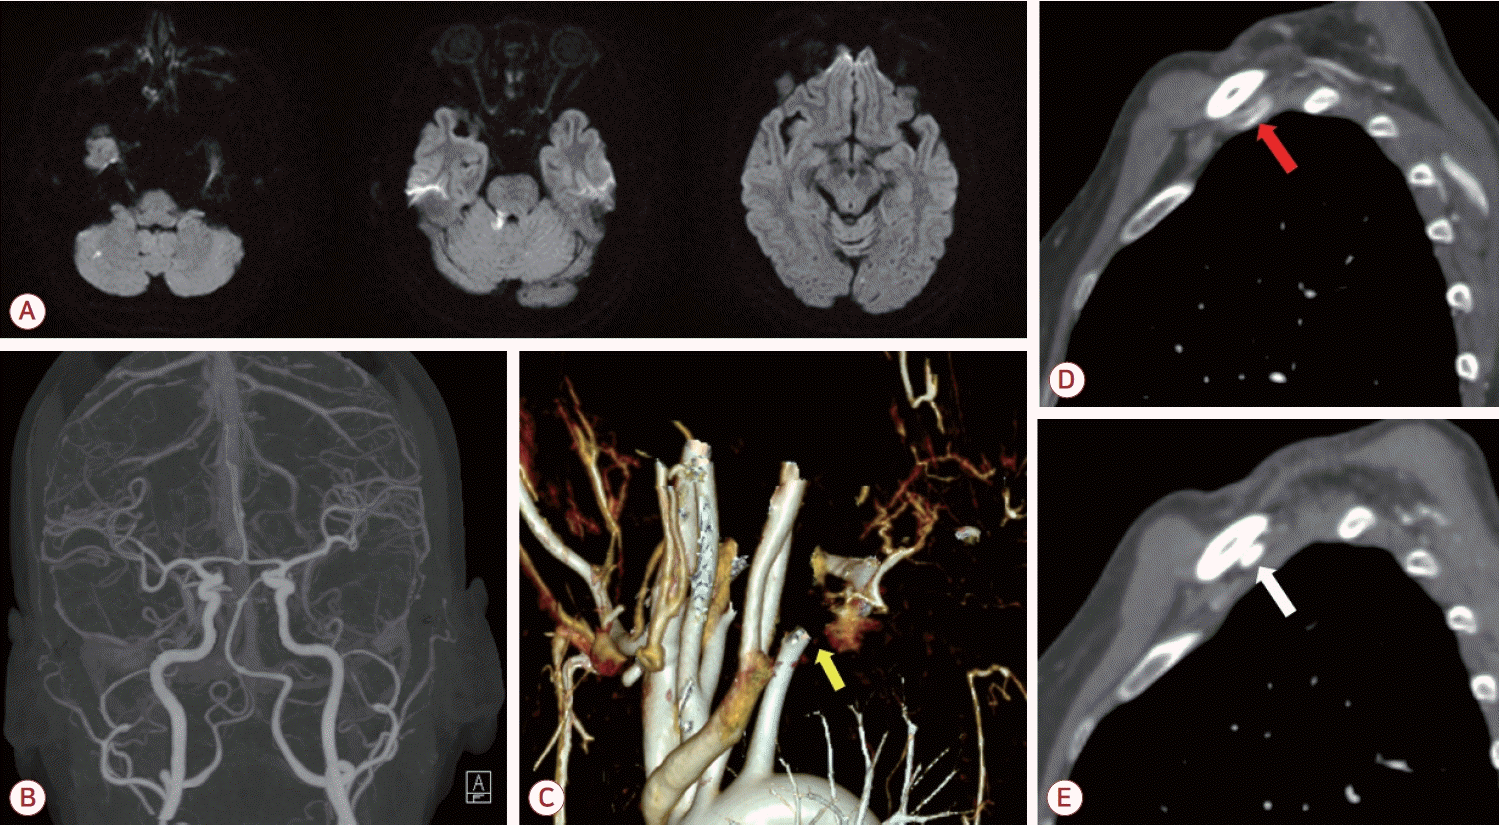

Figure 2.

Follow up images and photos after thrombectomy. (A) Reconstruction of upper extremity computed tomography (CT) angiography showing constriction of right subclavian artery and aneurysmal change of distal part (white arrow). (B) The thrombus obstructing the right subclavian artery. (C, D) Right cervical rib (yellow arrows) and clavicle (white arrow) interrupting flow of right subclavian artery (yellow arrowhead).

특이 질환이 없는 58세 여자가 내원 19시간 전 발생한 어지러움 및 이명을 주소로 응급실에 내원하였다. 1달 전부터 왼팔이 간헐적으로 저린 증상이 있었다. 내원 당시 활력징후에서 우측 상지의 혈압은 140/70 mmHg로 측정되었으나 좌측 상지의 혈압은 측정되지 않았다. 또한 맥박 64회/분, 호흡 16회/분, 체온 36.0℃로 측정되었다. 시행한 신경계 진찰상 우측 상하지의 실조 증상이 관찰되었으며 근력 약화 및 감각 증상은 확인되지 않았고 NIH뇌졸중척도(National Institutes of Health stroke scale) 2점이었다. 병적 반사나 안진 등은 뚜렷하지 않았다. 좌측 상지에서는 맥박이 측정되지 않았고 청색증이 관찰되었다.뇌자기공명영상의 확산강조영상(diffusion-weighted image) 에서는 우측 소뇌 및 소뇌다리, 좌측 후두엽에서 다발색전 양상의 고신호강도 병변이 보였다(Fig. 1-A). 또한 이후 시행한 뇌전산화단층촬영 혈관조영영상에서는 우측 척추동맥의 형성 저하 외에는 뇌내혈관 및 경동맥의 유의미한 협착은 관찰되지 않았다(Fig. 1-B). 또한 상지 전산화단층촬영혈관조영에서 쇄골하동맥의 폐색이 관찰되었으며(Fig. 1-C) 우측에 비해 좌측 쇄골과 경추늑골 사이 공간이 협소하고 혈류가 감소한 소견이 보였다(Fig 1-D, E). 혈액 검사상 D-이합체(D-dimer)는 3.21 μg/mL (정상, 0.0-0.5)로 상승되어 있었으며 항인지질인자, C/S단백질(protein C/S), 항트롬빈-III, 폰빌레브란트인자 등의 검사는 별도로 진행하지 않았다. 심전도, 경흉부 및 경식도심초음파, 24시간심전도 검사에서 심인성 색전증을 일으킬 수 있는 다른 질환은 발견되지 않았다.환자는 좌측 쇄골하동맥 폐색 및 동반된 뇌경색에 대해 입원하여 저분자량헤파린인 에녹사파린(enoxaparin) 1 mg/kg 하루 두 번으로 항응고 치료를 시작하였고 입원 3일차에 쇄골하동맥의 혈전색전제거술(thromboembolectomy)을 시행하였다(Fig. 2-B). 시술 후에 환자는 추가적인 뇌경색 병변이 발견되지 않았고 좌측 상지의 청색증이 호전되었으며 혈압 또한 우측과 차이를 보이지 않았다. 이후 에픽사반(apixaban) 5 mg 하루 두 번으로 약물 교체 이후 퇴원하였다. 시술 3개월 이후 추적 관찰한 혈관조영에서 이전에 보였던 혈전은 모두 제거되었고 새로운 혈전이 발생하지 않았음을 확인하였다. 또한 좌측 경추 늑골과 쇄골에 의한 쇄골하동맥의 압박 소견 및 이로 인한 말초 동맥류가 관찰되었다(Fig. 2-A, C, D). 이에 환자는 aTOS로 인한 뇌경색으로 최종 진단할 수 있었다. 환자는 항혈소판제인 아스피린 하루 100 mg으로 약물을 교체하였다. 환자에게 흉곽 출구증후군에 대해 경추늑골제거술 및 혈관성형술 등 수술적 치료를 권유하였으나 거절하여 약물 복용 유지 중에 있다.본 증례 보고에 대하여 고려대학교구로병원 의학연구심의위원회의 승인을 받았다(IRB No. 2025GR0163).